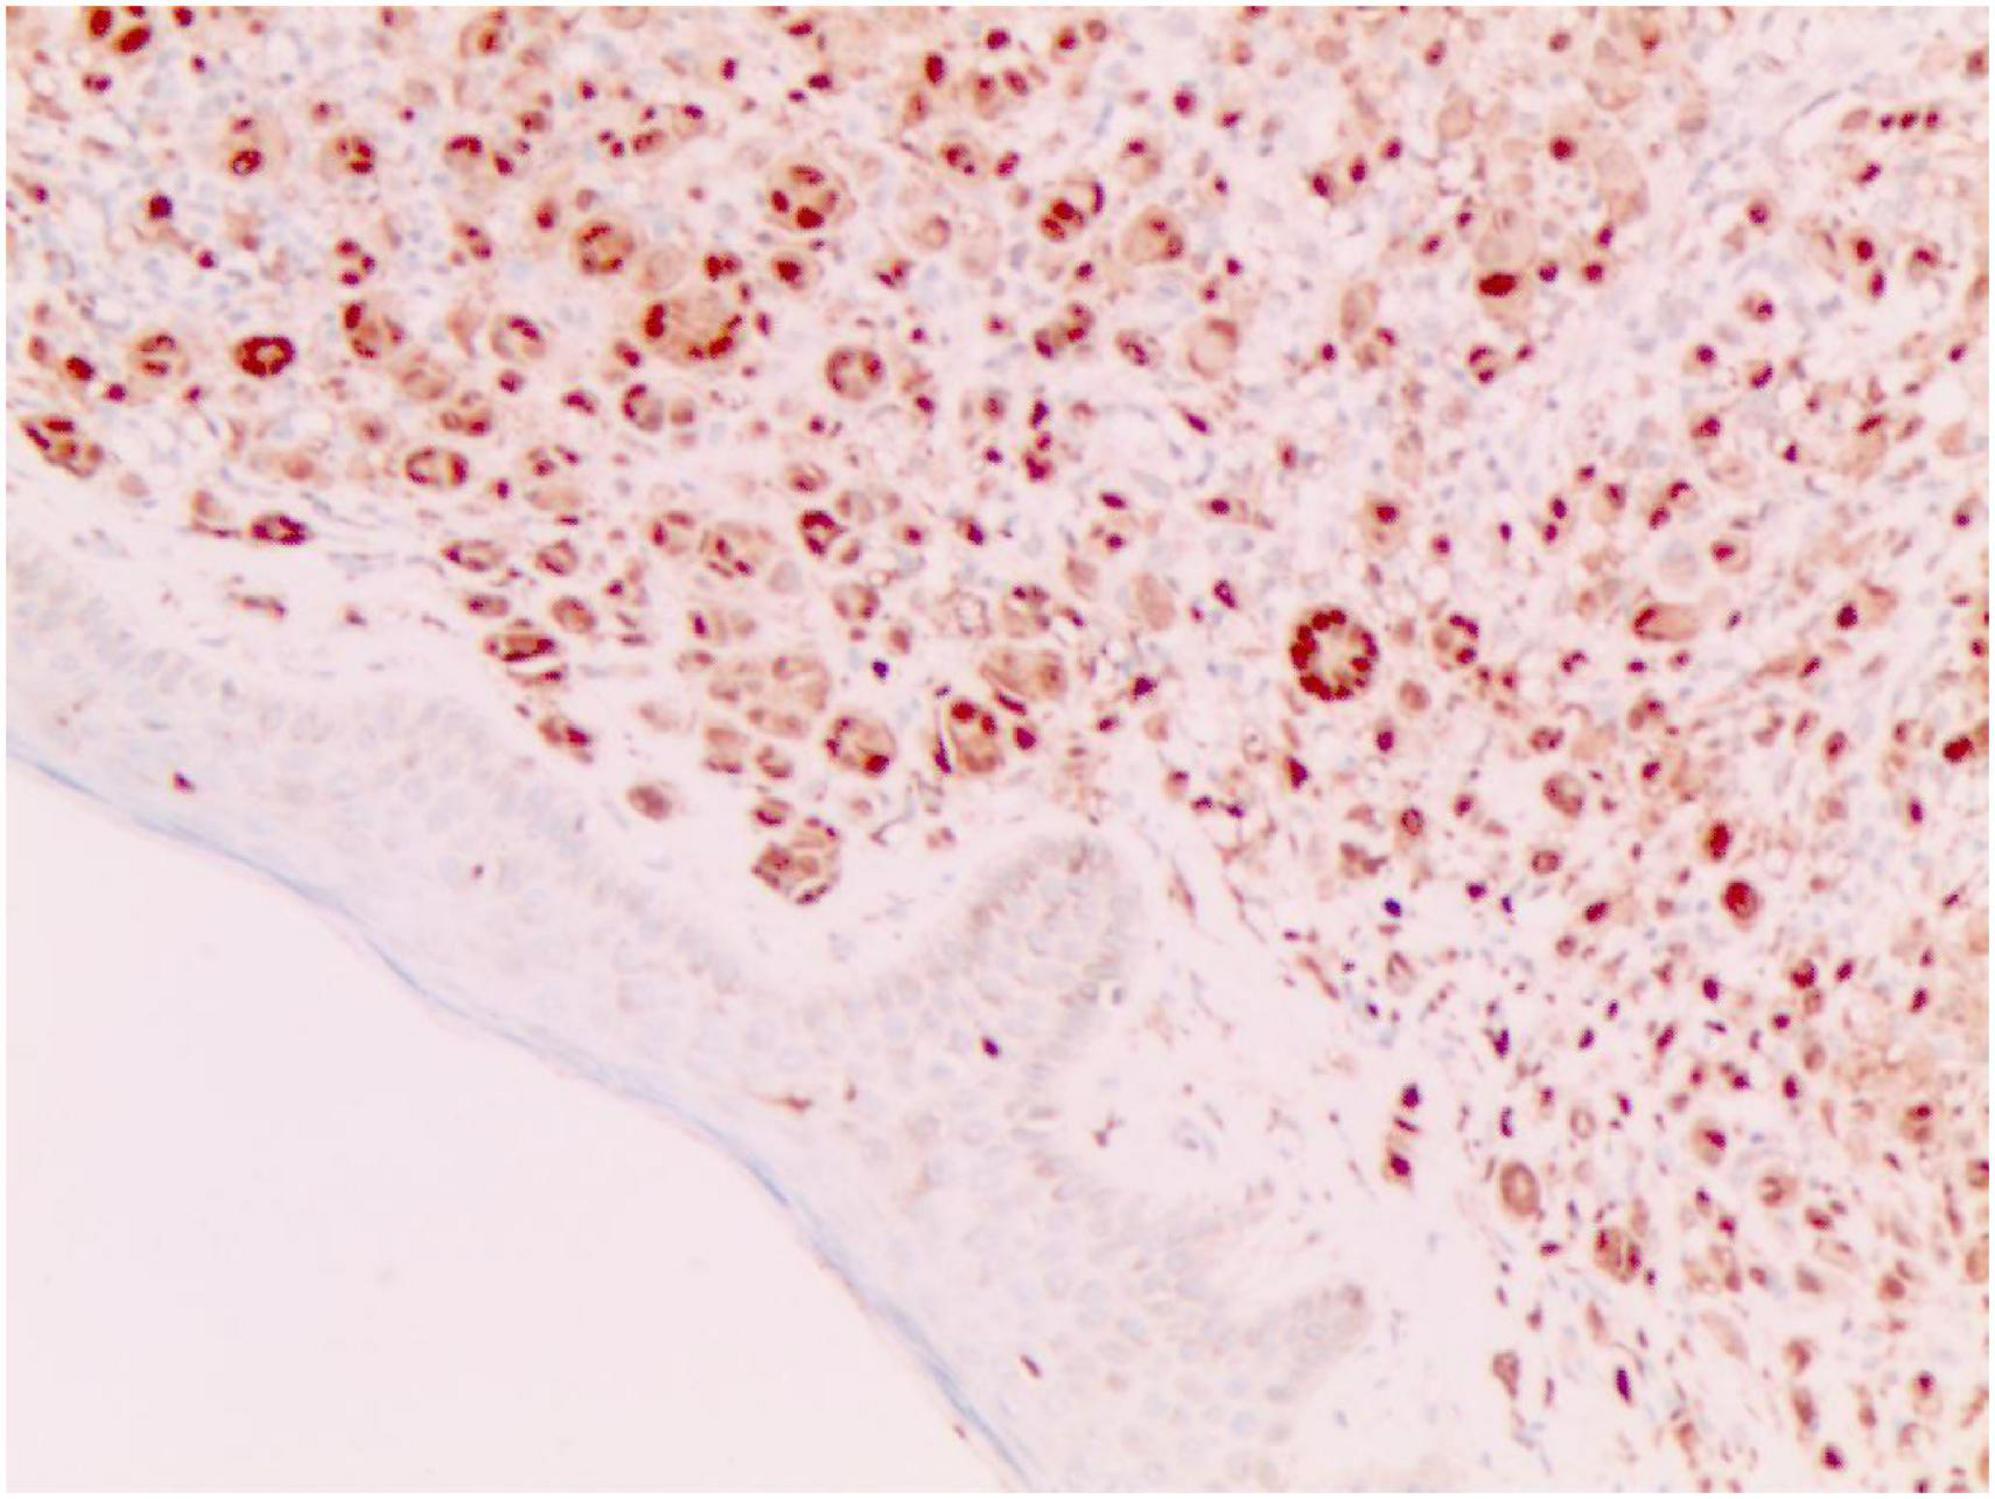

FIGURE 5

Vimentin (+) (Immunohistochemical staining, × 200).

No abnormalities were found upon routine blood and urine tests, coagulation function test and syphilis/HIV screening. Chest X-ray and abdominal B-ultrasound also revealed no abnormalities. Cutaneous histopathology: epidermal processes disappeared, and the dermis was diffusely infiltrated by substantial tumor cells that were in the nested or clumpy form. These polygonal tumor cells were round or oval, which had abundant cytoplasm filled with eosinophilic granules, and were stained pale pink. The cellular nuclei were small, hyperchromatic and centered, with few mitotic figures, and multiple nuclei were observed in some tumor cells. Immunohistochemistry: S-100 (+), CD56 (−), NSE (−), vimentin (+), CD68 (+), Ki-67 (+), cell proportion: 5%, p53 (−), SAM (+−). CK (−), calponin (−), CD163 (−), desmin (−), CD34 (−), CD45 (−), CD30 (−), SMA (1A4) (−), ALK (−), HMB45 (−), melan-A (−).

2.3.3 The immunohistochemical results

S-100 (+), vimentin (+), CD68 (+), Ki-67 (+), cell proportion: 5%, SAM (+ −). Immunohistochemistry rules out melanoma, tumors of lymphoid origin, smooth muscle tumors, keratoacanthoma, SCC, xanthoma, and dermatofibroma, etc.